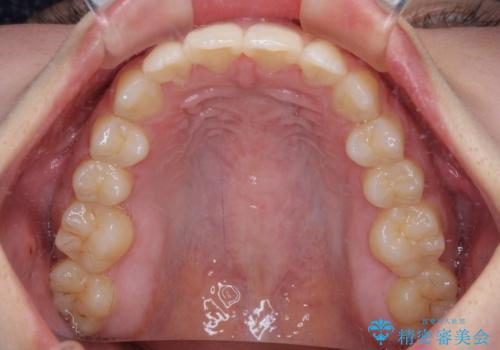

矯正治療終了後に速やかにオールセラミックブリッジを装着していくこととしました。

結婚式の予定があるとのことで、できる限り歯列を整え、挙式直前で残った乳歯を抜歯してブリッジの仮歯を装着するプランを立てたのですが、途中妊娠をされたため、麻酔をするタイミングを検討し、うまく前歯を整えることができました。